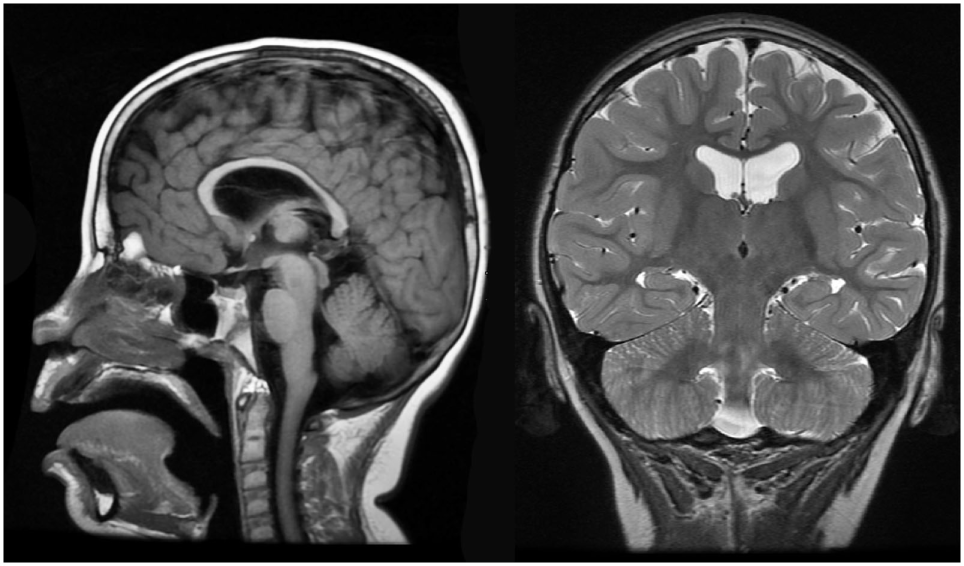

Brain MRI identified slight cortical atrophy involving the superior frontoparietal convexity bilaterally (Figure 4, right), thinning of the corpus callosum (Figure 4, left and right), and slight hippocampal asymmetry (Figure 4, right). There was also slight paucity of supratentotial white matter bilaterally, particularly along the centrum semiovale, which raised the consideration of a mild degree of periventricular leukomalacia.

Figure 4

Case 1 (WDR45) high resolution 3T magnetic resonance imaging brain scan. Sagittal T1 fluid attenuated inverse recovery imaging (left) demonstrates thin corpus callosum. T2 coronal imaging (right) demonstrates slight cortical atrophy and slight hippocampal asymmetry.